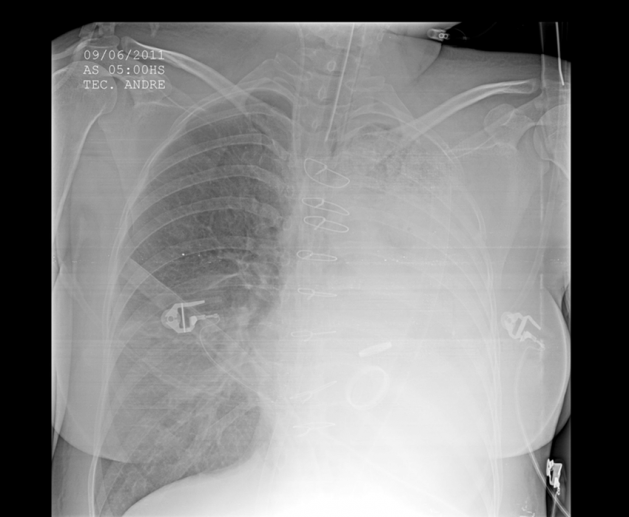

A 58 year old male with a history of HTN, HLD, and a 45 pack-year smoking history presents to the hospital in respiratory distress. He is holding an emesis bag filled with bright red blood. Using suctioning and a bougie, you successfully intubate him and obtain the below portable chest x-ray. What is the next best step to take in the management of this patient?

Answer: B. This patient is presenting with massive hemoptysis likely due to underlying malignancy. Massive hemoptysis is defined as >100 mL of blood loss in 1 hour or 1,000 mL of blood in 24 hours. Management of the airway is the most important first step, and the patient should be intubated with a 8.0 endotracheal tube if possible to prepare for future bronchoscopy. In order to keep blood from spreading to the unaffected lung, the patient’s lung that is bleeding should be placed down (in this case, the patient’s left lung is bleeding, therefore he is placed in the left lateral decubitus position). Selective intubation of a bronchus should be directed towards the unaffected lung to improve oxygenation to that side. In this case, the patient’s non-bleeding lung was the right side, therefore the patient should be intubated into the right mainstem bronchus. Once the patient is stabilized, further management includes obtaining a CT, potential bronchoscopy by interventional pulmonology, evaluation by interventional radiology, or Cardiothoracic surgery depending on the etiology of the bleeding and the patient’s clinical course.